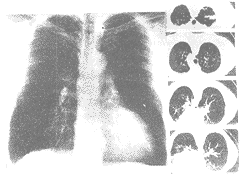

图3 复杂矽肺病人的胸片及CT片。可见大的融合团块周围有气肿带形成。虽然两种检查均可见融合团块,但CT可发现更多范围的融合区域

图2和图3显示经X线平片和CT两种方法检查对于小结节和融合团块的检出在多数情况下是一致的。图4显示个别经CT检查发现的融合团块经X线平片检查并未见有融合团块。

胸部CT和X线平片均可检出矽肺的融合团块(图3),但是CT检查较X线平片检查可发现更多的有融合团块的复杂矽肺病例,在本研究中经CT检查发现有47%病例为复杂矽肺,而经X线平片检查只发现有38%的病例为复杂矽肺。在X线平片检查未见融合团块的病例中,有5名经CT检查发现有融合团块存在(图4)。这点对于临床非常重要,因为这些团块有可能是矽肺早期的融合团块,也可能是结核或者是其他的肺部病变,如肺癌,而肺癌也是该年龄组较常见的一种疾病。在CT检出的5例融合团块病例中,有1例为肺癌,4例为矽肺融合团块。对融合团块的早期检出也很重要,因为这些融合团块以无功能的纤维团块代替了正常的肺组织,与呼吸系统症状的出现及肺功能恶化都密切相关[2]。此外这些复杂矽肺的预后也较单纯矽肺差[3]。